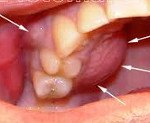

При периостите челюсти также обнаруживаются изменения со стороны полости рта, включающие гиперемию слизистой оболочки, наличие плотного болезненного инфильтрата или валикообразной припухлости с очагом флюктуации - поднадкостничного абсцесса. В дальнейшем, по мере гнойного расплавления надкостницы, экссудат проникает под слизистую оболочку десны, образуя подслизистый (поддесневой) абсцесс, откуда гной может периодически изливаться через свищевое отверстие в полость рта, принося временное облегчение.

При стоматологическом осмотре выявляются характерные клинические признаки периостита челюсти (гиперемия, инфильтрат, флюктуация и тд ). При одонтогенной инфекции в полости рта обычно имеется сильно разрушенная коронковая часть зуба, послужившего источником инфекции, с кариозной полостью и корневыми каналами, заполненные продуктами распада тканей. При перкуссии зуба отмечается болевая реакция.